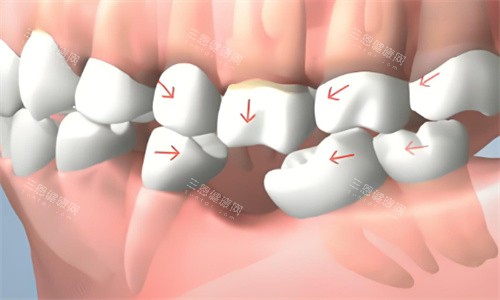

缺牙

牙周炎 牙龈萎缩 缺牙